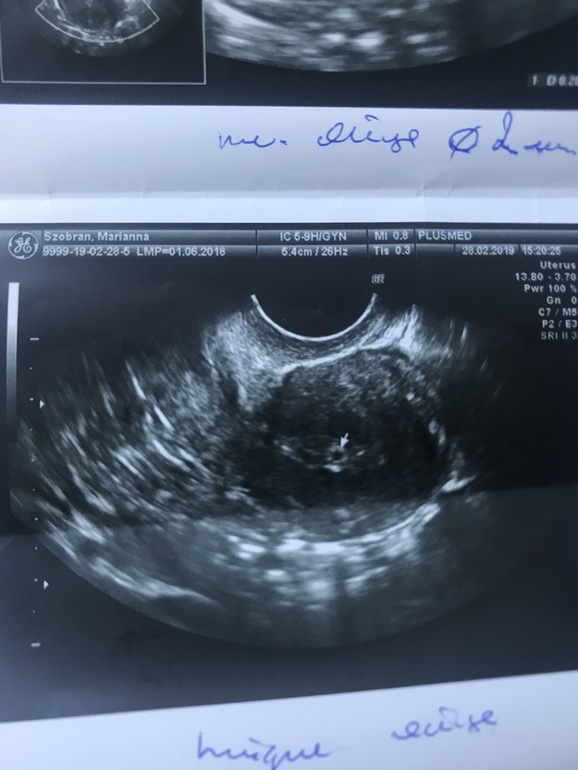

Разглядываем тесты // пока ждём результат ХГЧЗдравствуйте, девочки! Сначала хочу всех вас поблагодарить за такую колоссальную поддержку!!! Была я на УЗИ 2 часа назад. ВБ исключили, Слава Богу!Нашли плодное яйцо в матке, 2 мм, но после месячных эндометрий сдулся. Но!!!! В обеих яичниках нашли по созревающему фолликулу! Я в шоке с себя! Врач в шоке! Сказала в понедельник ещё раз пересдать ХГЧ и 7-8 марта опять на УЗИ. Девочки, как вам?Плодное яйцо маленькое? Врачка шансов даёт очень мало.